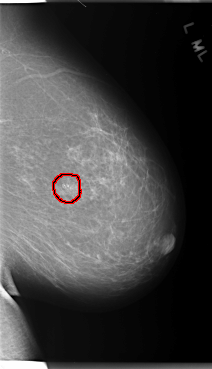

C_0106_1.LEFT_CC

LEFT_CC LINES 5952 PIXELS_PER_LINE 3152 BITS_PER_PIXEL 12 RESOLUTION 50 OVERLAY

FILE: C_0106_1.LEFT_CC.OVERLAY

TOTAL_ABNORMALITIES 1

ABNORMALITY 1

LESION_TYPE CALCIFICATION TYPE PLEOMORPHIC DISTRIBUTION CLUSTERED

ASSESSMENT 5

SUBTLETY 5

PATHOLOGY MALIGNANT

TOTAL_OUTLINES 1

BOUNDARY